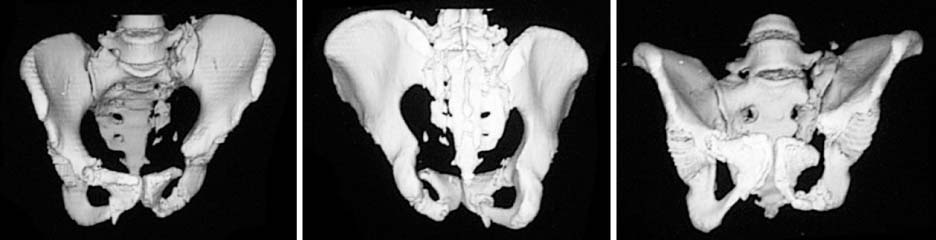

Fig. 4

Three-dimensional computed tomography shows superior and posterior migration along with internal rotation and flexion deformity of the left hemipelvis.

Fig. 4 Three-dimensional computed tomography shows superior and posterior migration along with internal rotation and flexion deformity of the left hemipelvis.